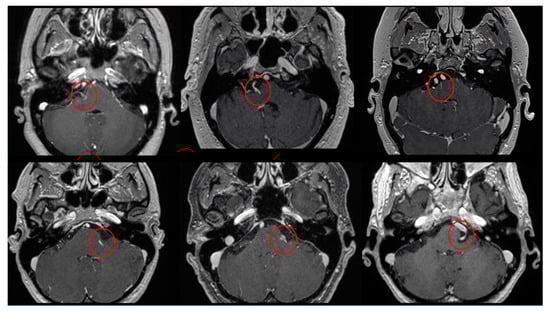

Figure 3.

Axial view of MRI in T1WI with gadolinium and FIESTA sequences demonstrating the presence of the Prevedello sign (an arterial loop attached to the pons near the exit of the facial nerve), highlighted by the red circles.